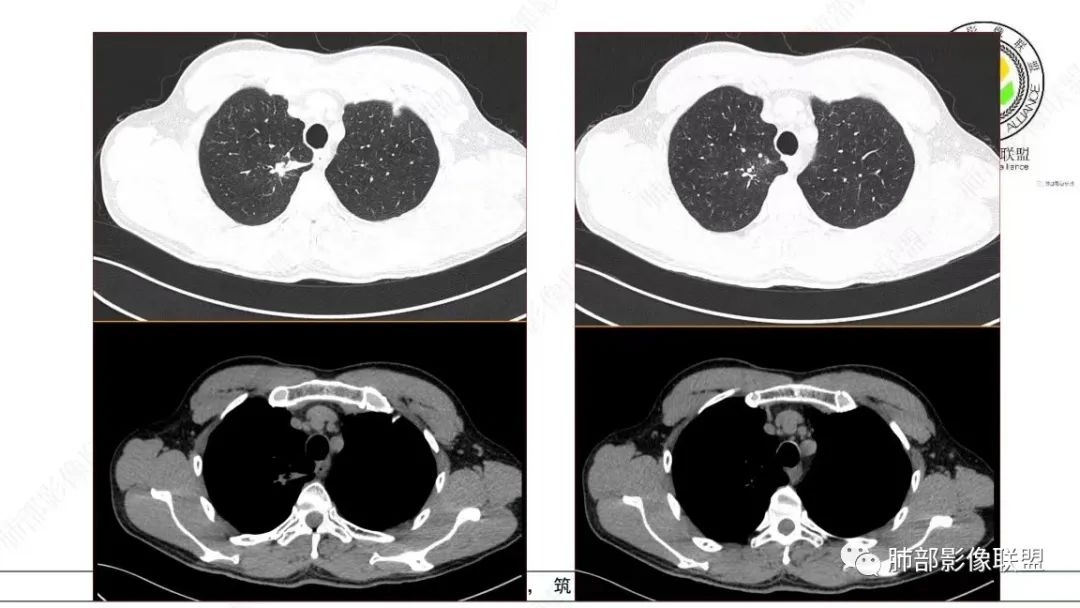

这个病例还可以深挖,图像有点少,我感觉部分层面可疑少许磨玻璃。最难鉴别的是结节型黏液腺癌,特别是细支气管腺瘤的收缩力比较弱的时候。这个病例收缩力太强,结节型黏液腺癌不太好解释。结合病理及影像表现,这个病例最终诊断:倾向于细支气管腺瘤、合并一些非特异性的感染、支气管内粘液栓形成。细支气管腺瘤,疑难。实性的细支气管腺瘤,更疑难。再合并感染,难上加难。不讲理的一个病例。

影像诊断

本研究对22处BA的CT影像进行分析,发现以下方面对诊断本病有一定提示意义:①病变部位:本组病例均为周围型病变,多位于下叶,且以胸膜下区为主,与既往研究结果一致。本病细支气管黏膜上皮的起源赋予了其特有的位置分布。②类型:本组GGO14处,实性结节8处。Chang等收集的14处BA中,GGO6处、实性结节8处,与既往研究结果基本一致。此外,部分学者报道呈空洞表现的BA。由此可见,BA的影像表现多样,但主要表现为GGO和实性结节。③大小:本研究显示BA普遍较小,最大径约(0.9±0.7)cm,95%的病变不超过2.0cm。王蓓等、高何等分别纳入8例、15例BA,病灶平均最大径均为1.0cm,与本研究结果一致。④形态:本组BA无论表现为GGO还是实性结节,其形态不规则且边缘毛糙,仅少部分体积较小的BA可呈类圆形或椭圆形,与Kamata等的研究结果相似,推测BA的形态学改变与肿瘤无包膜有关。⑤伴发征象:本研究中BA多伴有中央或外周空泡征、细支气管充气征及血管征,其中以中央空泡征最具特征。刘芳兵等报道2例表现为GGO的BA均伴空泡征;苏雷等报道11例BA中,伴有空泡征8例、血管征10例。可见空泡征和血管征对诊断本病具有重要意义。上述征象与镜下瘤内、瘤周常见细支气管及伴行的厚壁血管有关。此外,胸膜牵拉征、分叶征及毛刺征罕见。⑥强化方式:实性结节表现的BA增强扫描呈延迟性显著强化,部分病灶动脉期可见血管造影征,血管走行自然,未见破坏。血管造影征与镜下病变常见细支气管动脉束穿行相符,此征象也反映了肿瘤位于细支气管周围的定位。⑦随访中病灶保持稳定或缓慢增长。此段内容及病例图片摘自并感谢,黄勇教授、王越老师-细支气管腺瘤的CT表现,发表于中国医学影像杂志。